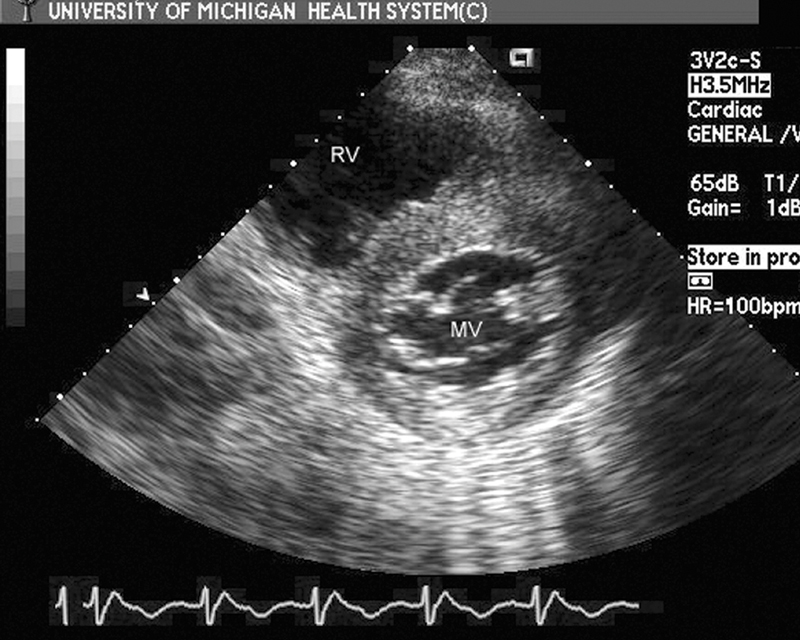

فحوصات تشخيصية لبعض امراض القلب والشرايين التاجية